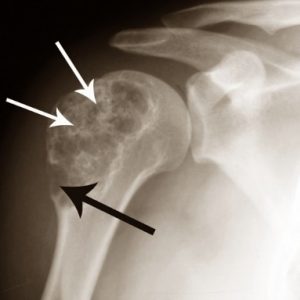

Диагностические мероприятия при подозрениях на энхондрому основываются на рентгенографическом исследовании. При рентгене пораженного сегмента ноги выявляют участок просветления в костной ткани.

При доброкачественных опухолях светлая область на снимках имеет четкие границы и не приводит к изменению кортикального слоя кости, в отличие от злокачественных новообразований.

Энхондрома — это опухоль, располагающаяся в толще костной ткани. Обычно она представлена одиночным очагом с ярко выраженными контурами. Этот очаг вздувает кость, меняя ее контуры. В центре этого очага обычно располагается однородное просветление с четкими контурами.